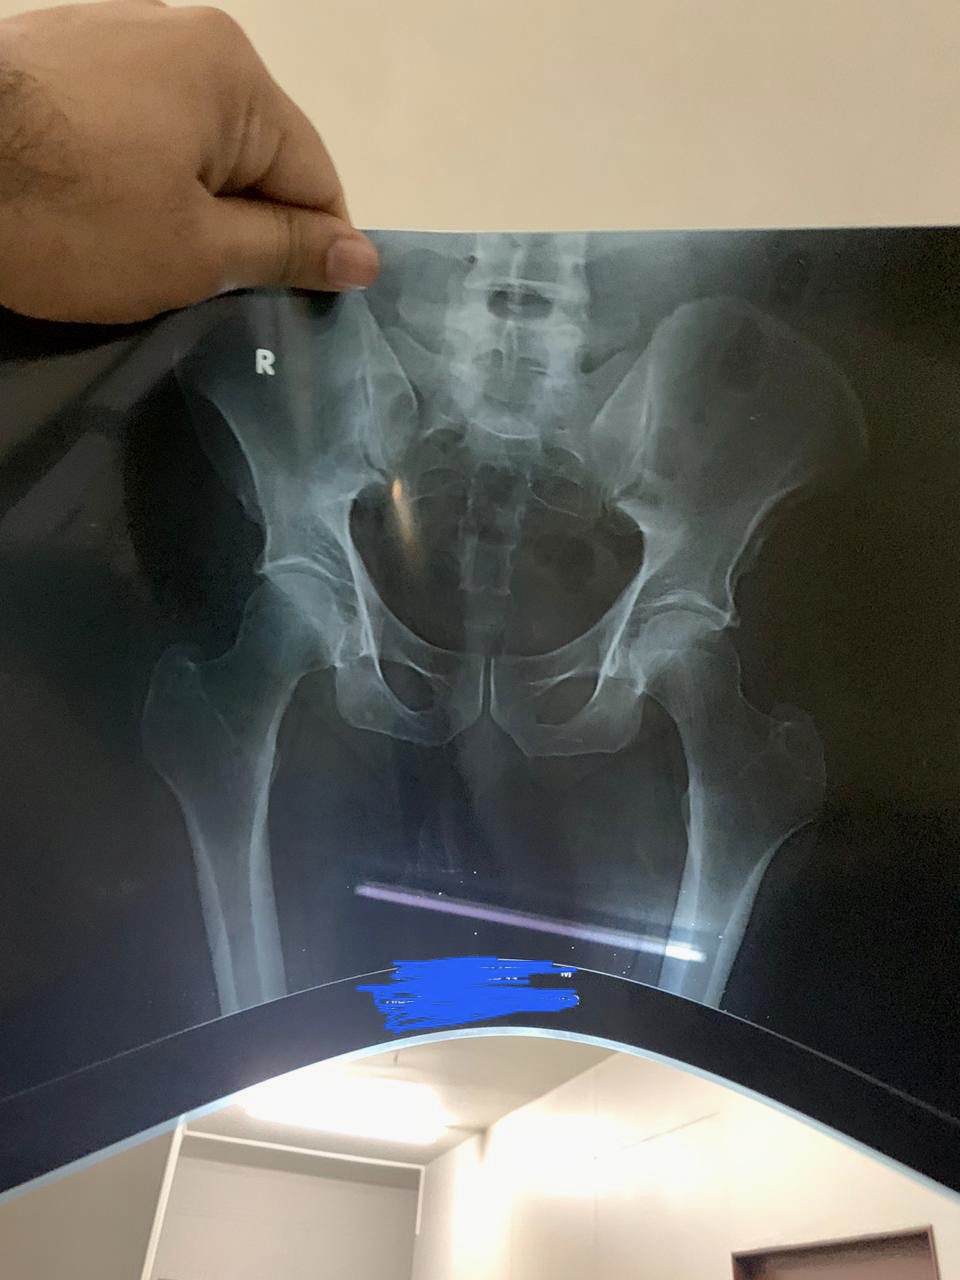

Kindly identify the fractures in the attached X Rays. It was a road Accident. Kindly tell which fractures are present or any other abnormality is there ?

there is a bimaleolar fracture of the ankle need fixation (surgery)

bimalleolar needs surgery.

Bimalleolar be operated ...

It need surgical fixation with screw and plate.....

It’s an ankle fracture which immediately needs surgical procedure.

Yes there are fractures present as seen in X-ray ( bi- malleolar ) plz visit orthopedic surgeon to get the surgical fixation as soon as it is possible..

Bimalleolar frac needs urgent surgery

Bimalleolar ankle fracture,needs surgical fixation only.

it's Pott fracture. needs surgery